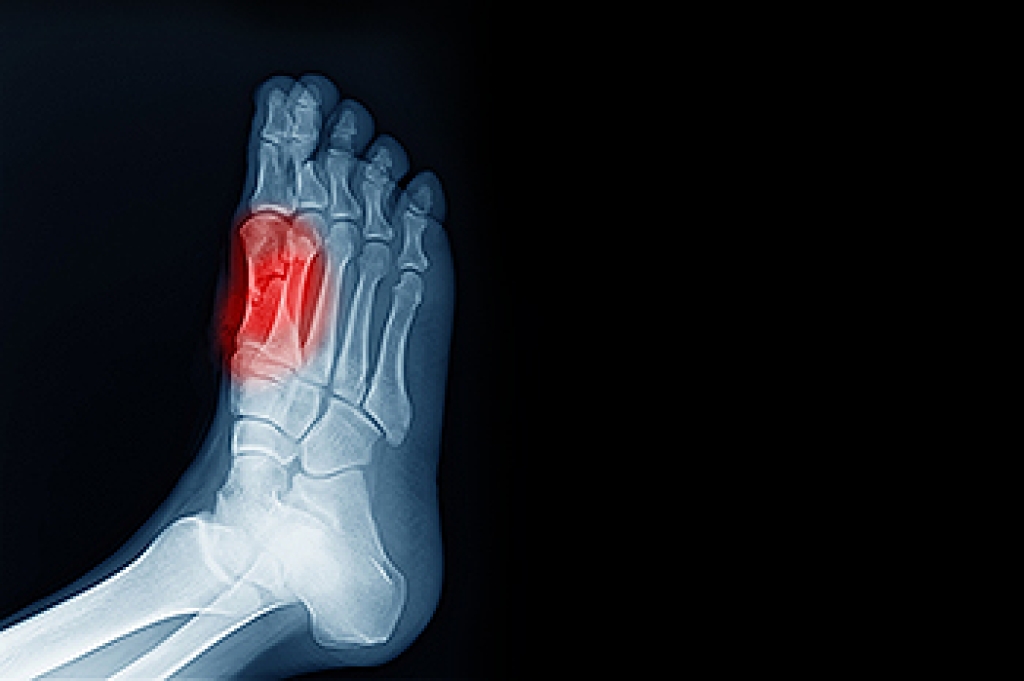

Sesamoiditis is a painful foot condition that affects the sesamoid bones, which are two small bones located beneath the base of the big toe. These bones help absorb pressure and assist with movement during walking and push off. When they become inflamed, pain can develop around the ball of the foot, especially under the base of the big toe. Common symptoms include aching or sharp pain while walking, standing, or bending the toe, along with swelling and tenderness in the area. Sesamoiditis is often caused by repetitive stress, high impact activities, or increased pressure on the forefoot. A podiatrist can diagnose the condition, recommend activity modification, provide protective padding or orthotics, and develop a treatment plan to reduce inflammation. If you have pain under your big toe, it is suggested you schedule a visit with a podiatrist who can accurately diagnose and treat what may be going on.

Sesamoiditis is a condition of the foot that affects the ball of the foot. It is more common in younger people than it is in older people. It can also occur with people who have begun a new exercise program, since their bodies are adjusting to the new physical regimen. Pain may also be caused by the inflammation of tendons surrounding the bones. It is important to seek treatment in its early stages because if you ignore the pain, this condition can lead to more serious problems such as severe irritation and bone fractures.